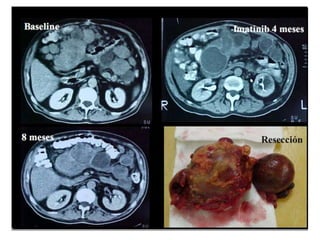

• Si no puede lograrse R0 , un tratamiento neoadyuvante (6 a 12

meses) con IM es la recomendación.*

Manejo de los GISTs avanzados*

• La citorreducción quirúrgica está desaconsejada.

• Imatinib (IM) es el tratamiento estándar del GIST metastático a la

dosis de 400 mg/día. (indefinidamente)

• 65 -70 % alcanzan una respuesta parcial y 15 -20% enfermedad

estable.

• Los beneficios clínicos son muy rápidos.

• El tiempo medio de las respuestas radiológicas es de 12-15

semanas. (Por PET respuestas en 24 hs!!!)

• Las metástasis hepáticas y peritoneales responden adquiriendo un

aspecto quístico en TAC (degeneración hialina y disminución del

número de células viables)